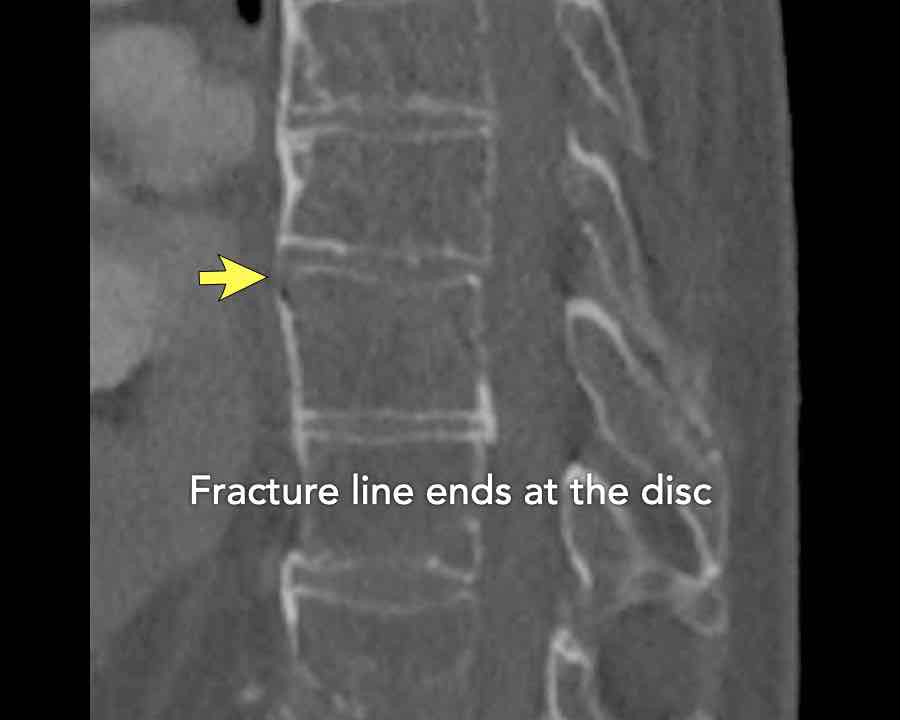

Extension distraction is characterized by:

- Distraction of the tension band on the anterior side.

- Any horizontal or oblique fracture line through vertebral bodies anteriorly with separation on both sides.

- Widening of intervertebral disc space.

Scroll through images.

What are the findings?

Findings

- C injury? No.

- Signs of a rigid spine?

Yes, so be aware of potentially very subtle B3 injury. - A subtle fracture on the anterior vertebral body is seen (arrows).

Conclusion

Injury type B3.